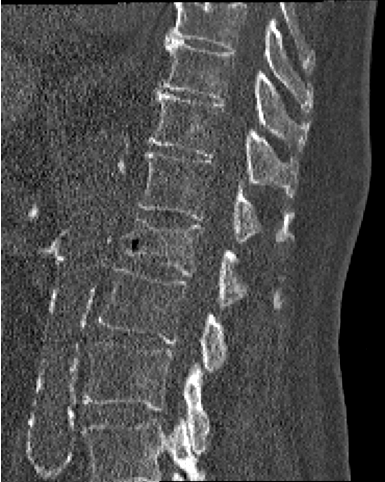

Although the model demonstrated high performance overall, we observed several failure cases. In some cases like Figure 4a, vertebrae were missed completely. This is because vertebral centroids that are too close in z axis may cause blurred boundaries in segmentation, so these vertebrae centroids are deleted in the post-processing. In some cases like Figure 4b, vertebrae were mismatched to incorrect labels due to rare vertebral mutation, or like in Figure 4c, due to artifact of metal implants. These issues highlight the challenges of accurate vertebra detection and segmentation in complex clinical scenarios.

Refer to caption

(a) Missed vertebrae due to close centroids

(b) Label mismatch caused by vertebral mutation

(c) Label mismatch caused by metal implant artifacts

Figure 4: Visualization of representative failure cases. Each subfigure shows, from left to right, the original CT image, ground truth mask, and the predicted mask.